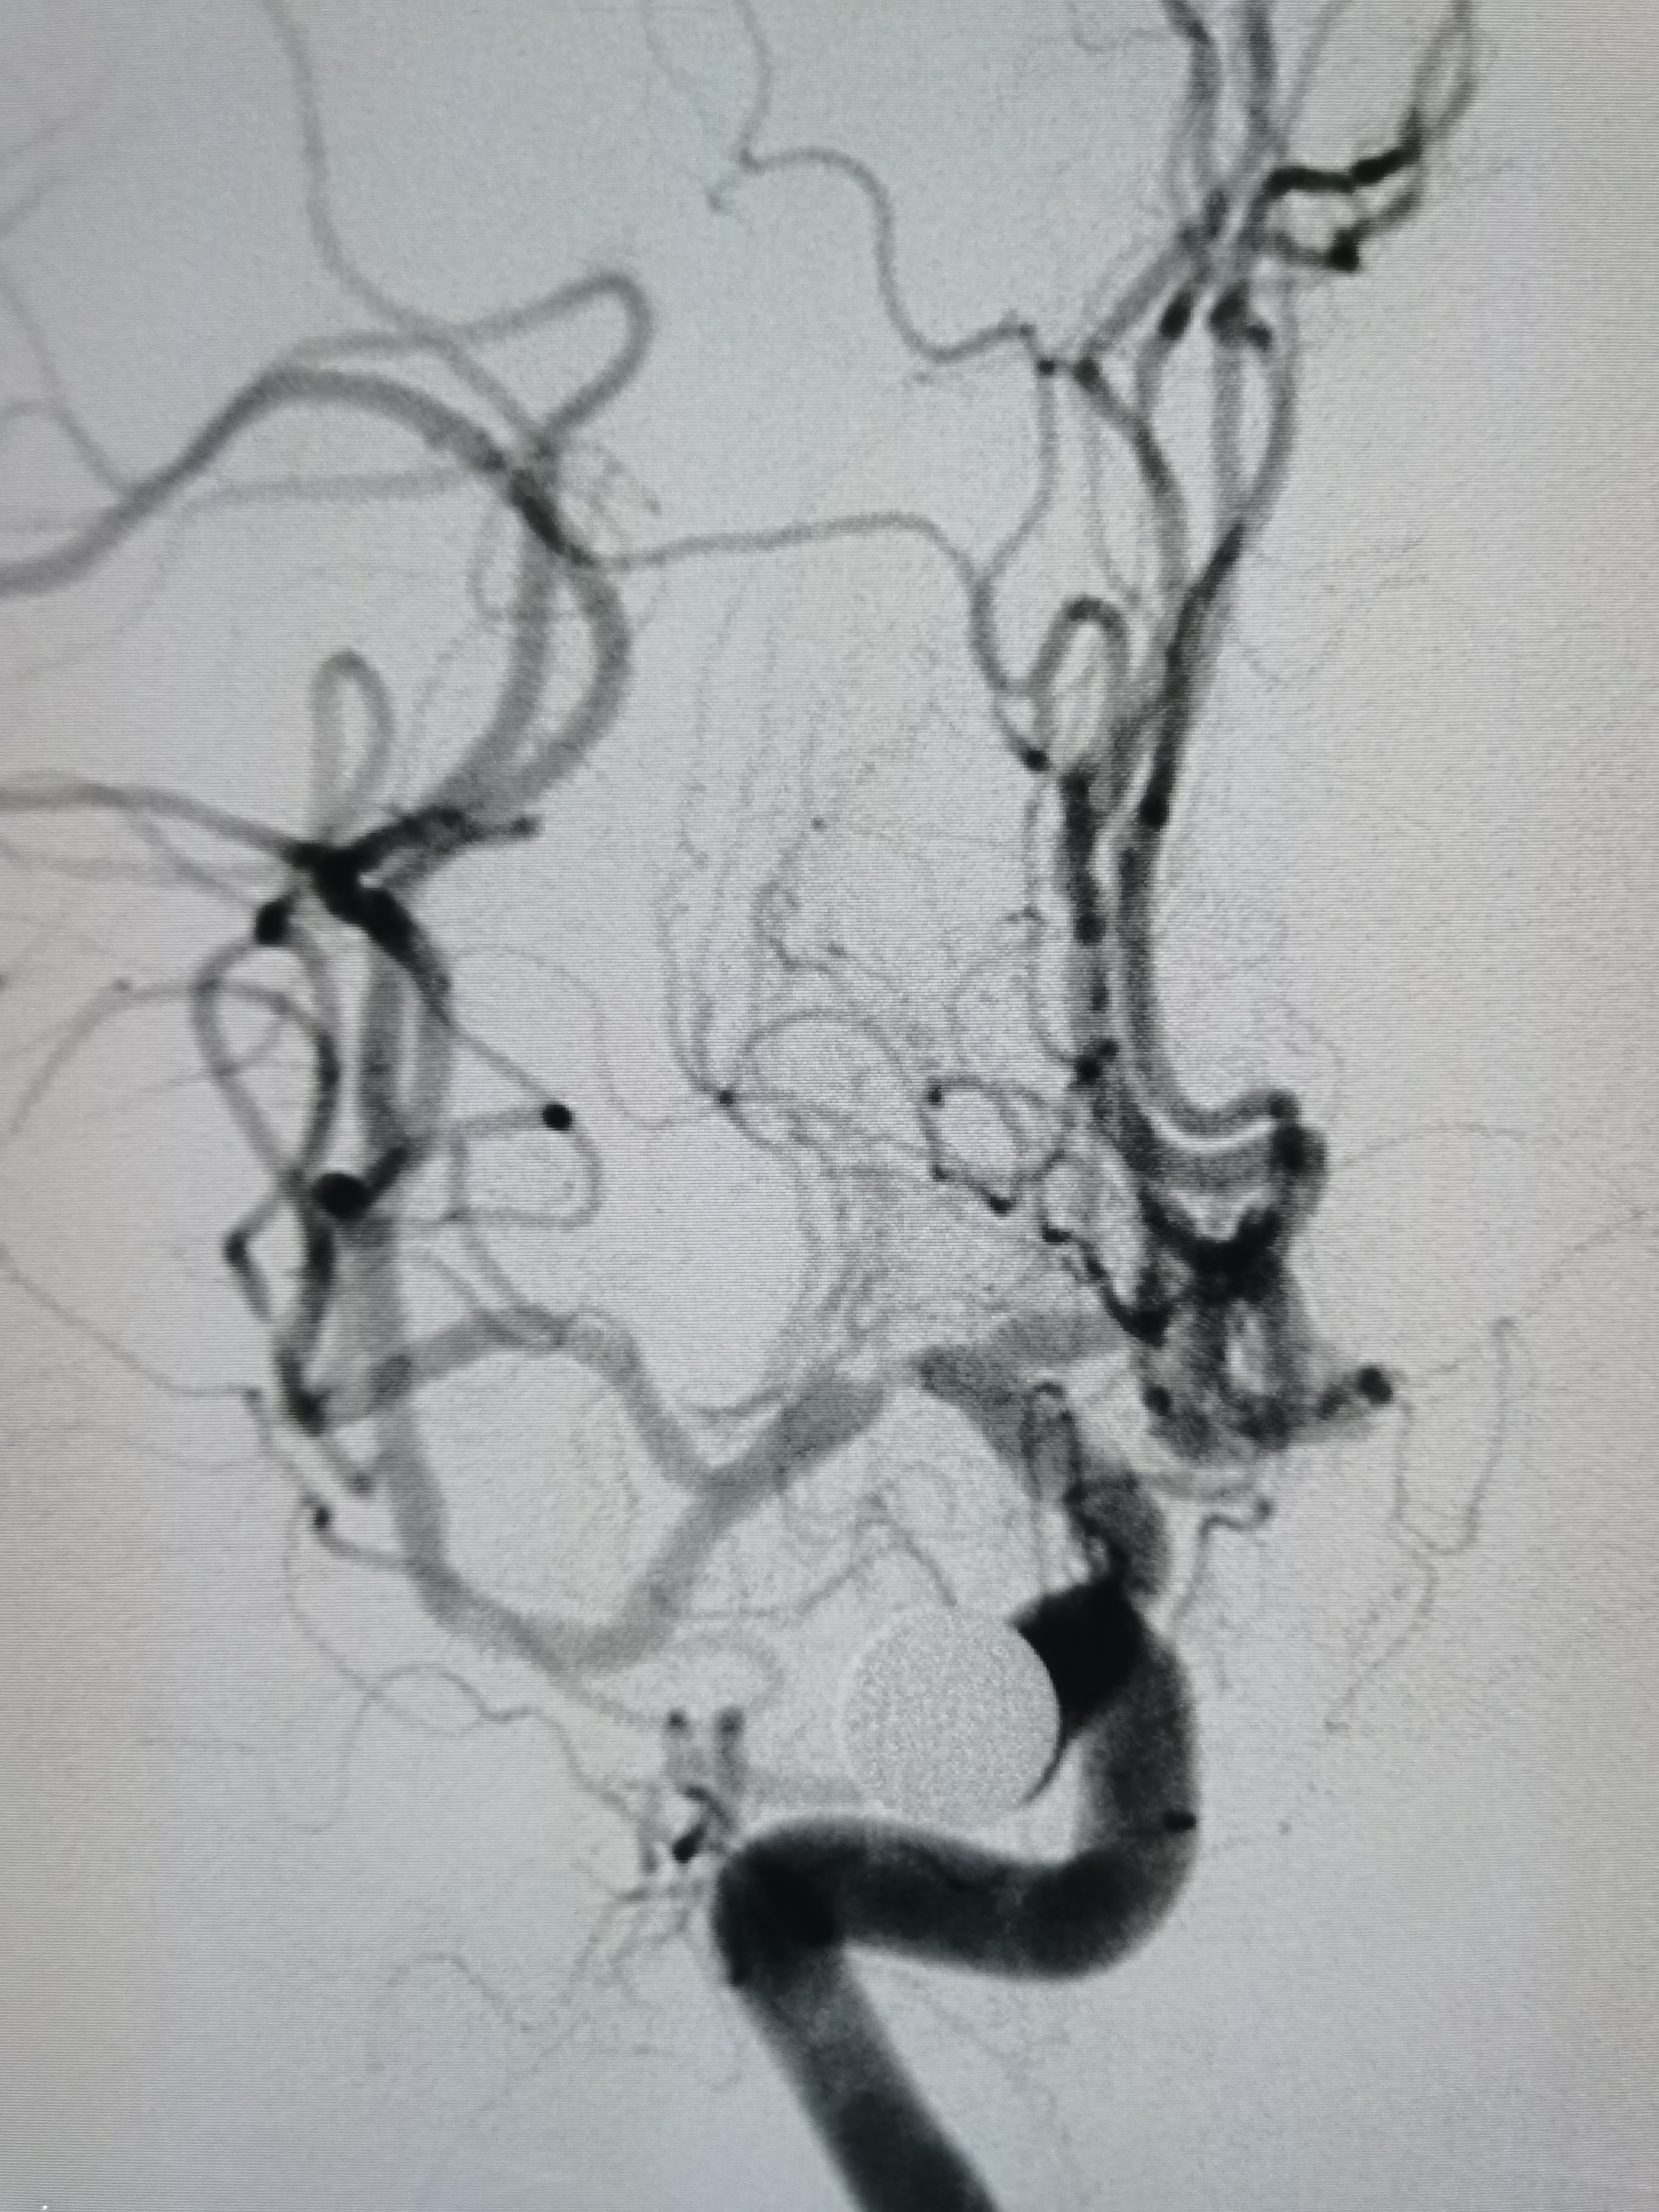

8F导引导管+6F中间导管建立通路,微导丝携微导管顺利通过病变,交换Transend300导丝,路径图下送入2.5/15颅内扩张球囊,缓慢加压至6atm。

在球囊到位前后分别给予导管内推注替罗非班行穿支冲洗,避免扩张过程中豆纹动脉闭塞。

球扩后造影见狭窄解除,豆纹动脉显影良好,远端血供改善,未见夹层征象。

正位造影见狭窄解除,颅内血流通畅。

观察15分钟后造影未见明显弹性回缩。

侧位造影见颅内血流通畅。

球囊扩张后狭窄解除,决定不再植入支架,撤出导丝造影见血管通畅,遂逐级撤出各级导管,结束手术。